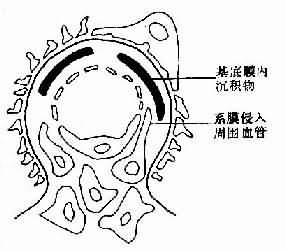

图12-16 膜性增生性肾小球肾炎Ⅱ型示意图

肾小球系膜增生并侵入周围毛细血管,血管壁增厚,毛细血管基底膜致密层内有高电子密度致密沉积物,粗大呈带状